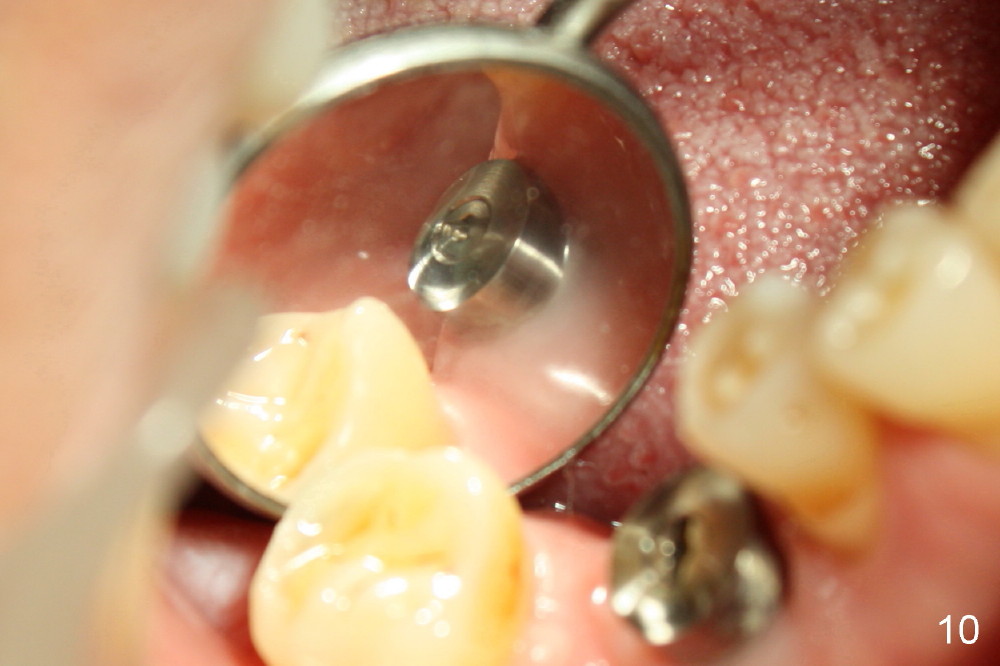

Fig.9 and 10 are taken 1 month 3 weeks postop.